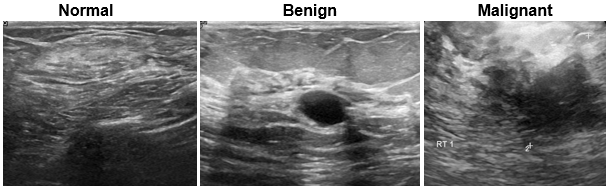

Breast Ultrasound Images (BUSI)

| The Breast Ultrasound Images (BUSI) data set contains 2-D breast ultrasound images [26]. The data set contains 133 normal images, 487 images with benign tumors, and 210 images with malignant tumors. Each ultrasound image has a corresponding tumor mask image for training semantic segmentation networks. The tumor mask labels have been reviewed by clinical radiologists. The size of the data set is approximately 197 MB. Download the BUSI data set from the MathWorks website. zipFile = matlab.internal.examples.downloadSupportFile("image","data/Dataset_BUSI.zip"); filepath = fileparts(zipFile); unzip(zipFile,filepath) Load

the data as an image datastore using the

imageDir = fullfile(filepath,"Dataset_BUSI_with_GT"); imds = imageDatastore(imageDir,IncludeSubfolders=true,LabelSource="foldernames"); For an example showing how to process this data for deep learning, see Breast Tumor Segmentation from Ultrasound Using Deep Learning. | Semantic segmentation |